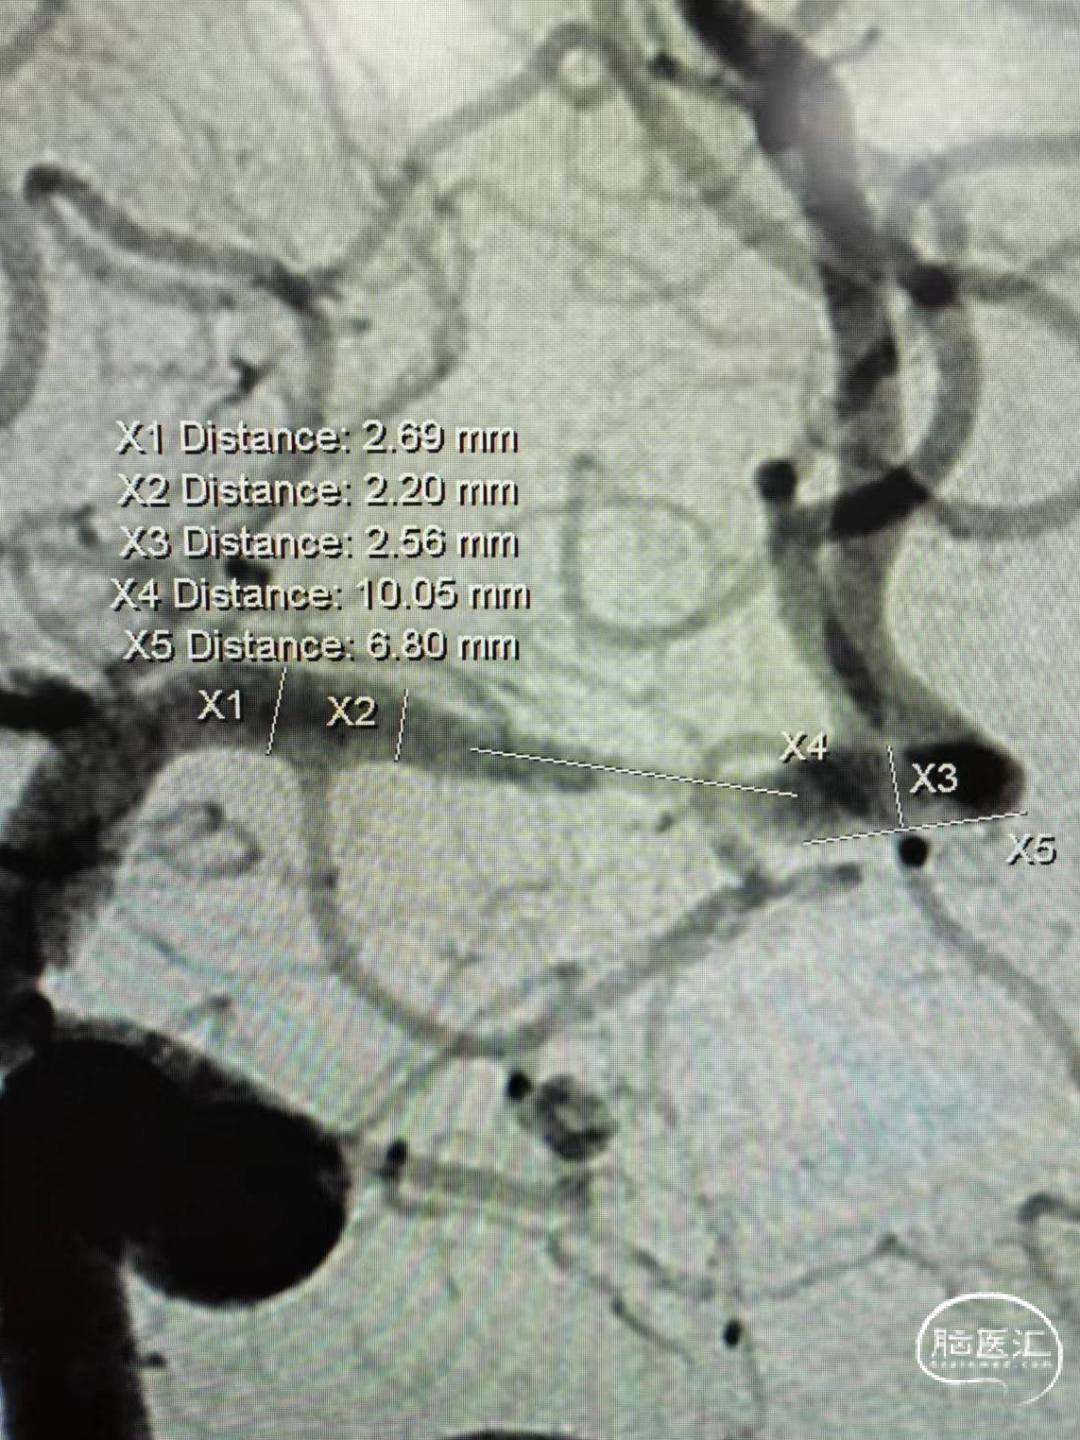

➢DSA:LM1重度狭窄

➢看远—Fastunnel®头端的着陆区问题

3D旋转展开,远端距离最大值也是8mm,很纠结!